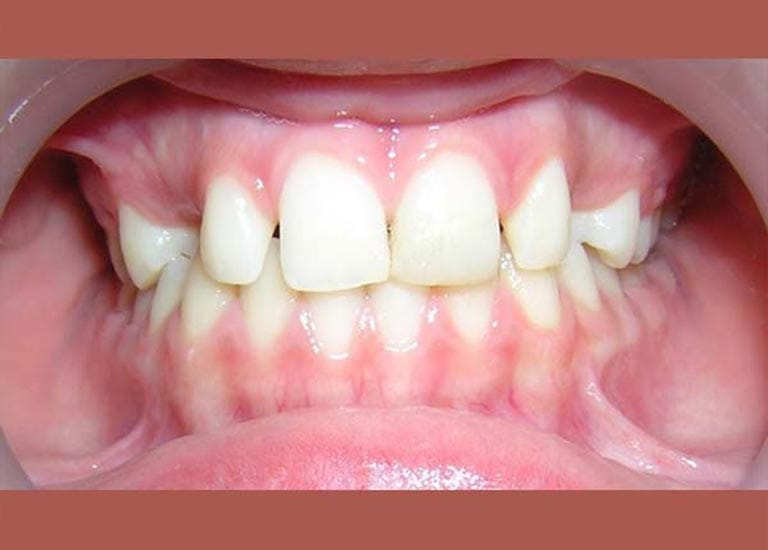

BEFORE

كانت المشكلة الرئيسية في هذه الحالة هي وجود ناب علوي منطمر بالكامل في عظم الفك، وغير قادر على البزوغ بشكل طبيعي.

كما تظهر الصور، تم إنزال الناب المنطمر بنجاح ورصفه بشكل مثالي مع بقية الأسنان. النتيجة هي ابتسامة كاملة وصحية، واستعادة سن مهم جداً لوظيفة الفم وجمال الابتسامة.